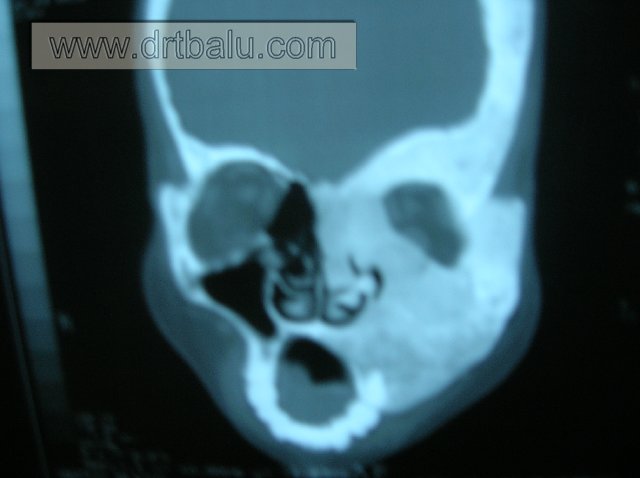

Coronal CT image of nose and sinuses showing fibrous dysplasia

CT scan shows a lesion that is confined to the interior of the bone with no soft tissue component. It is helpful in distinguishing fibrous dysplasia from a malignancy. Features of malignancy include osteolysis, destruction of sclerotic margins, and cortical destruction with soft tissue extension. The bony lesion shows a homogenous matrix with obliteration of maxillary sinus cavity.